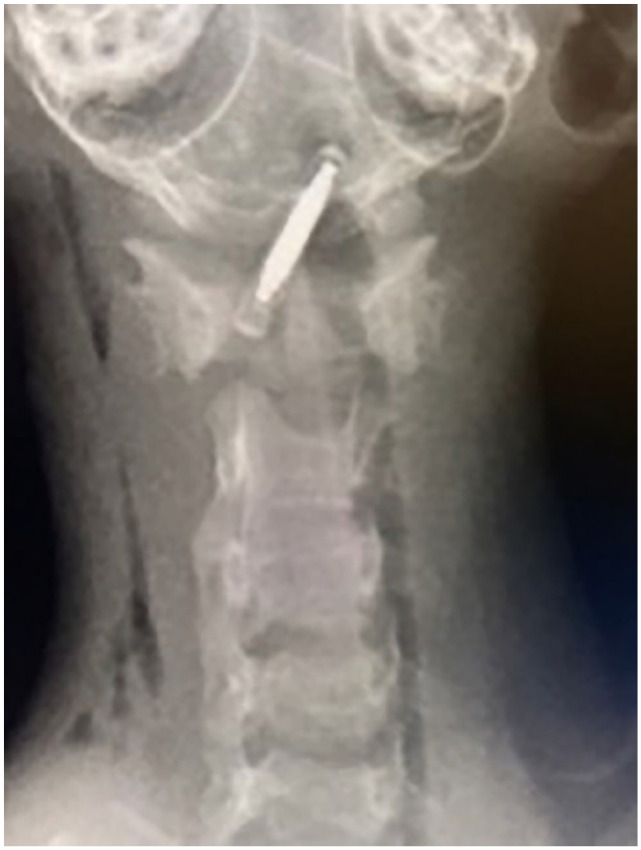

Case summary: A 2-month-old kitten was presented for ataxia and depressed mental status after implantation of a pet identification microchip. Radiographs were taken immediately by the referring veterinarian and showed a longitudinal metallic foreign body (electronic microchip) within the cervical vertebral canal at the craniocervical junction. A CT examination 2 days after the incident showed cranial migration of the microchip ventrally to the caudal brainstem. Ventral basioccipital craniectomy was immediately performed to retrieve the microchip by a ventral approach to the caudal brainstem. Postoperative recovery was uneventful and the cat was discharged 2 days later. At the 2-week follow-up, neurological examination of the cat was normal. No long-term complications were reported.

Relevance and novel information: This case report describes the intradural migration of a microchip and surgical removal via ventral basioccipital craniectomy.